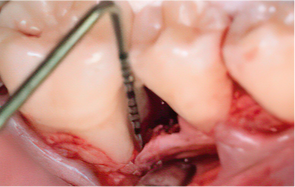

Emdogain Surgical Procedure

STEP 01

Gingival incision

-

STEP 02

Scaling and Root Planing (SRP)